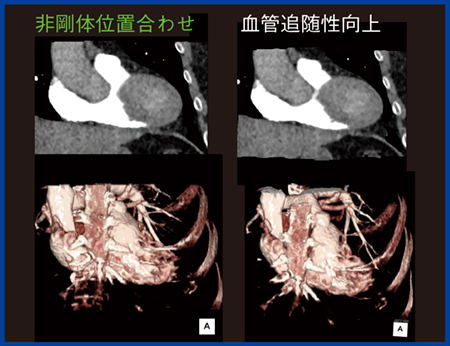

われわれは,PhyZiodynamicsを用いた冠動脈のダイナミックCT Angiography(CTA)について2016年に報告した1)。冠動脈のダイナミックCTでは,320列CTでテストインジェクションによる冠動脈のピーク時の撮影と,レトロスペクティブECGゲーティングによる拡張期のみの連続10フェーズの“boost scan”によって冠動脈の連続撮影を行う。これにPhyZiodynamicsを適用することで,低線量でかつノイズの少ない滑らかな動態画像を得ることができる。PhyZiodynamicsでは,元画像のフェーズ間を任意の断面で補完することで仮想的に時間分解能を向上する予測補完技術(図1),CTの逐次近似画像再構成技術とPhyZiodynamicsの予測補完技術を組み合わせたノイズ低減(図2),非剛体位置合わせ機能による息止め不良などのモーションアーチファクトを低減するモーションコレクション機能(図3)などによって,冠動脈のダイナミックCTAの視覚化が可能になった。

図3 PhyZiodynamicsの要素技術〜非剛体位置合わせ